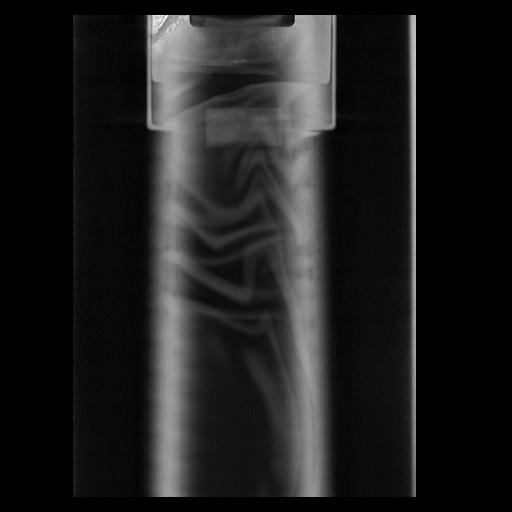

32 PULMON,CE,Coronal,3.000,PULMON,Coronal,